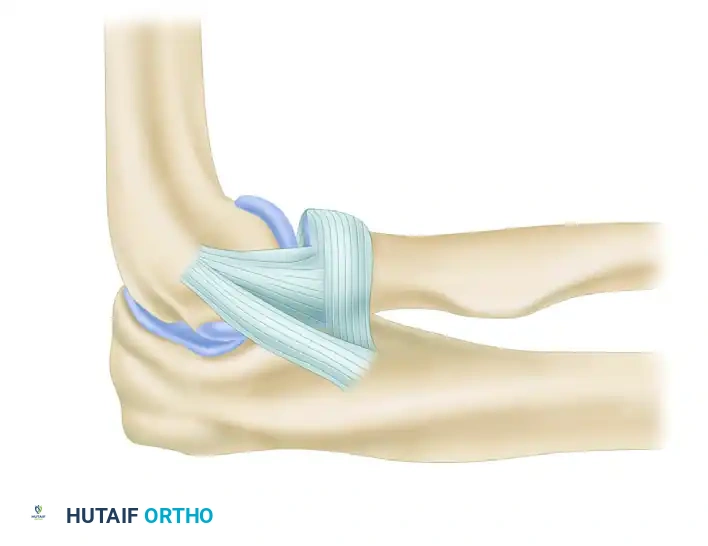

3. Ligament Imbrication and Advancement

Before graft placement, the native, attenuated tissues are managed. Perform an imbrication and advancement of the ulnar band of the radial collateral ligament and the radial part of the radial collateral ligament. This is accomplished using a Bunnell suture technique, placing the sutures through drill holes at the anatomical origin of the ligament in the humerus. This plicates the posterior and anterior capsule, providing a robust secondary restraint.